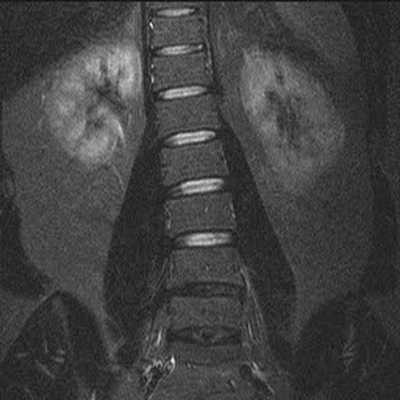

Гемангиомы на снимке МРТ поясничного отдела позвоночника в коронарной проекции

Показания и противопоказания для МРТ пояснично-крестцового отдела позвоночника